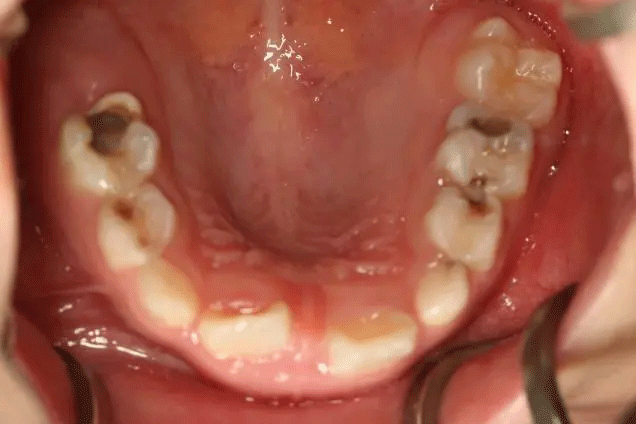

在門診中發(fā)現(xiàn)

來口腔科檢查的孩子

有些牙齒都已經(jīng)爛得很嚴重了

甚至牙齒幾乎都爛光僅剩下牙根

孩子不喊疼,家長很少會帶來看牙

5 歲兒童乳牙齲患率為 70.9%

10 個小孩子里, 7 個有蛀牙